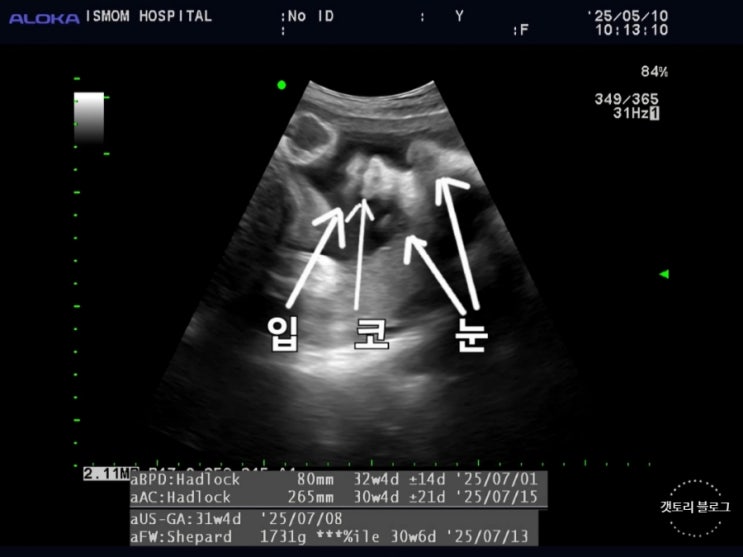

[32주] 공포의 배뭉침과 아기 위치

32주가 되면서 배뭉침이 심해졌다. 이전에도 누웠다 일어날 때 가끔 배가 딱딱해지는 현상은 있었지만 이제...